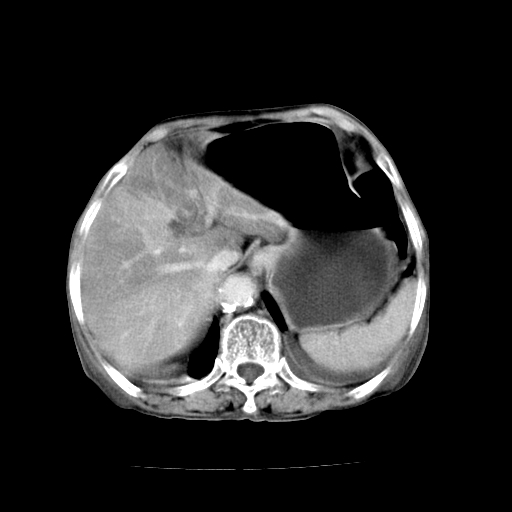

标题: CT19149:女,68岁,腹胀、恶心两周。 [打印本页]

女,68岁,腹胀、恶心两周,先做ct平扫,当时家属不同意强化,6天后家属要求增强扫描。

1、胃窦癌; 2、局灶性脂肪肝。

1、胃窦癌?建议行胃镜!; 2、局灶性脂肪肝。

不均匀脂肪肝,胃腔改变须结合钡餐或胃镜观察